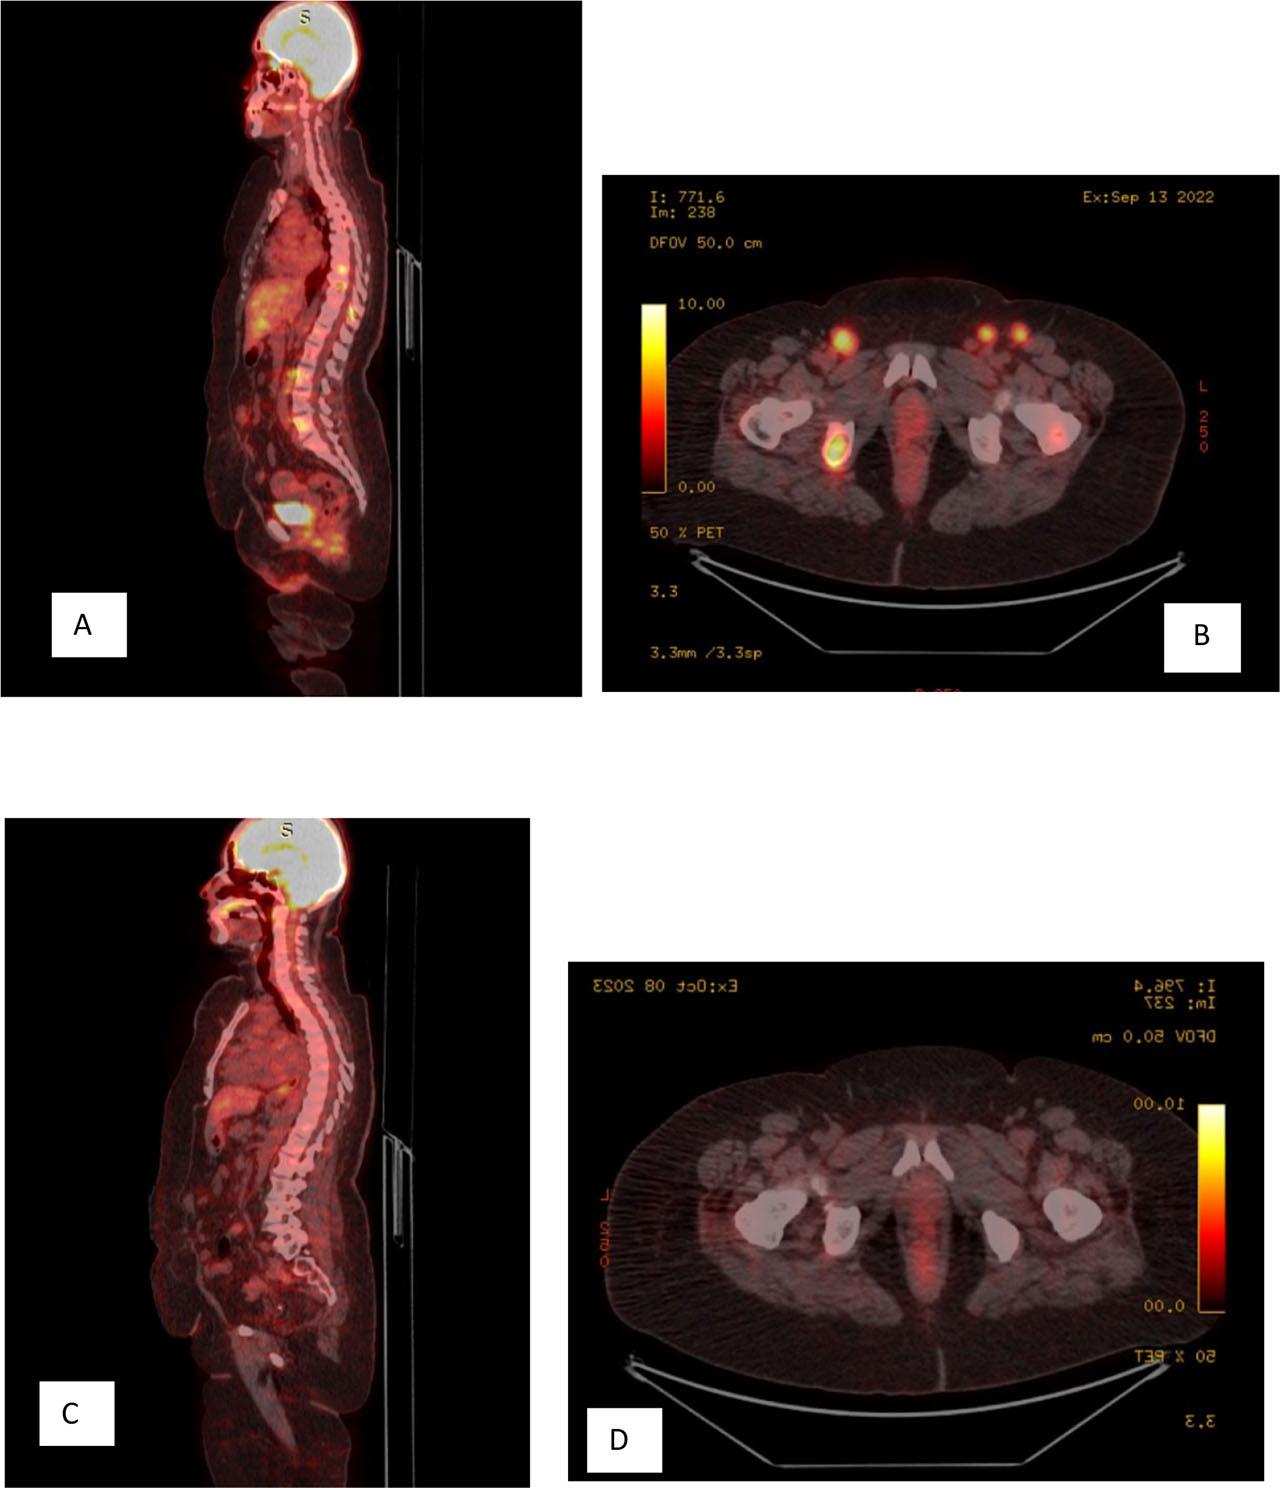

A and B: PET Scan before hormonal treatment, C and D: PET Scan after hormonal treatment.

Upon referral, we carried out a complete diagnostic workout: mammogram and breast color Doppler sonography were done and the results were normal. No solid or cystic lesions were detected in the bilateral breast quadrants. There were no findings in favor of ductal ectasia in the bilateral retroareolar area. No lymph nodes of pathological size and characteristics were observed in the bilateral axillary region. Echocardiogram was normal with an ejection fraction of 65%. Positron emission tomography (PET) scan results showed the following: bilateral inguinal LAP with the largest lymph node measuring 1.6 × 1.6 cm and having a maximum standardized uptake value (SUVmax) of 10.6 on the left side, multiple abdominal LAP involving extensive areas, including the iliac, common iliac, para-aortic, and aortocaval regions, and multiple lytic bone lesions observed in all appendicular bones, including D8, D9, D10, L5, and the left iliac bone.

Following the completion of chemotherapy, the patient underwent a period of rest for 2 weeks before undergoing a PET scan. The results of the PET scan were promising, indicating a complete morphological and metabolic response in the vulva and lymph nodes, as well as a complete metabolic response in the bones. At this point, the patient was presented with two options: continuing chemotherapy or opting for follow-up visits. The patient decided against continuing chemotherapy and chose to proceed with regular follow-up visits.

Malignant accessory breast tissue is a developmental variation where abnormal breast tissue is present in addition to the usual breasts. This unusual presentation makes the case exceptionally rare. The diagnostic process involved extensive testing, including a negative PET scan, mammogram, and breast ultrasound. However, the biopsy results clearly indicated that the lesion was of breast origin, further supported by elevated tumor markers associated with breast cancer. Considering the comprehensive assessment and all available evidence, this conclusion becomes the most plausible and fitting explanation for the patient's condition. The decision was made to initiate hormonal therapy. The PET scan results revealed a complete response to the hormonal therapy. There was no indication of hypermetabolic tumor lesions at the excision bed of the primary site and no evidence of hypermetabolic pelvic or abdominal lymph nodes. In addition, non-metabolically active sclerotic bone lesions were observed, with no newly developed hypermetabolic metastases detected throughout the scanned body (Figures 7–10).